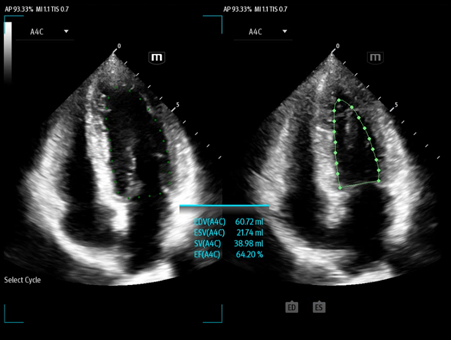

MindrayŌĆśs critical Ultrasound solutions drive improvements in care quality. Integrating advanced hemodynamic Ultrasound features, we can guarantee the highest standard of clinical care. The unique interoperability of Ultrasound and Vital sign data, we can provide comprehensive patient status data, to help inform clinical decisions, enhance clinical efficiency and, ultimately, improve patient outcomes.